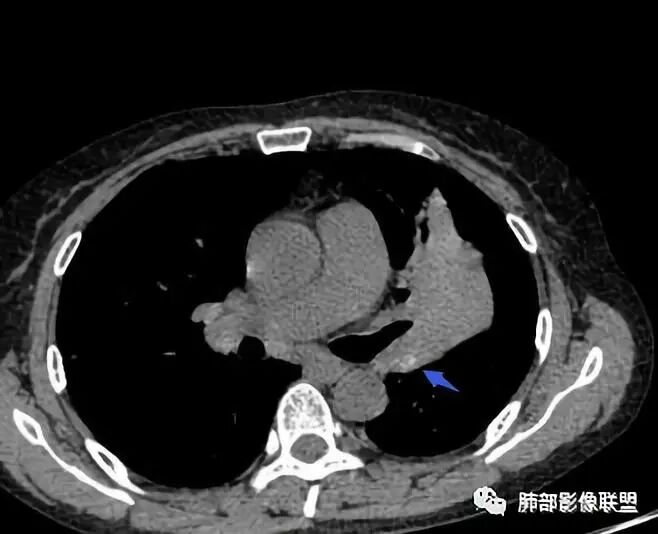

上叶支气管堵塞处稍萎缩、凹陷,附近壁增厚,内可见小点状钙化

树芽征、小叶间隔增厚,淋巴结, 内部血管走形自然

分析:支气管粘液栓、支气管堵塞处萎缩、钙化,支气管通畅处部分扩张,树芽征——提示结核。

看这些钙化

前壁不厚,附近钙化灶太多,所以觉得结核一定要考虑,加上树芽征,就更支持。

支气管因为软骨,密度偏高,从这连续性看,支气管这一段的壁不厚,只是周围有病灶。

支气管壁软骨存在且连续,没有被破坏掉,支气管壁局部通畅,提示支气管壁没破坏,那么近端支气管癌肿不考虑。远端有树丫征,病灶周围很多钙化,所以结核一定有。